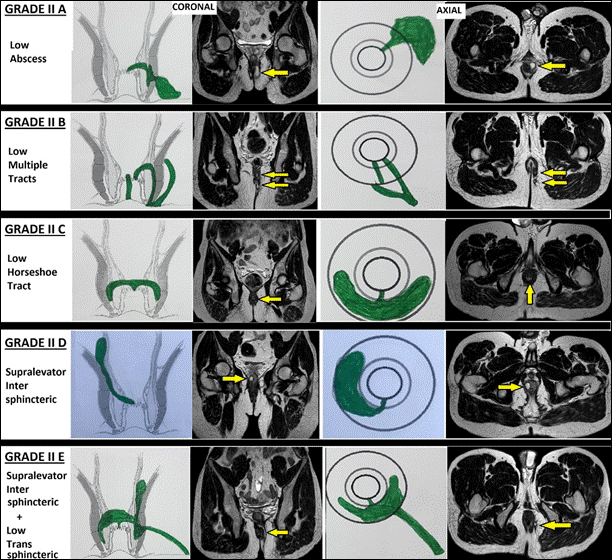

II |

Rò thấp gian cơ thắt hoặc xuyên cơ thắt ngoài (liên quan < 1/3 chiều cao cơ thắt ngoài) II-A:Có ổ áp-xe II-B:Có nhiều đường rò II-C:Rò dạng móng ngựa II-D:Rò gian cơ thắt lan hoàn toàn lên trên cơ nâng hậu môn (supralevator) II-E:Rò xuyên cơ thắt thấp (<1/3) nhưng có nhánh gian cơ thắt lan phía trên cơ nâng hậu môn (supralevator) |